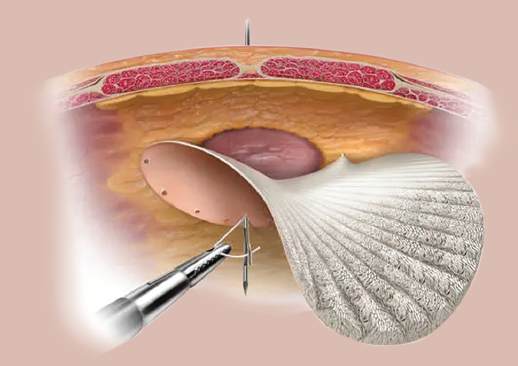

La técnica quirúrgica del abordaje laparoscópico de la reparación de la hernia ventral incluye el protocolo de evaluación con valoración preoperatoria, la selección del material protésico, que en caso de mérito fue un material dual (Dual Mesh) que contiene una segunda capa separadora de tejido, la cual puede ser de material permanente o absorbible; la correcta colocación de los 3 trócares abdominales, la instauración del neumoperitoneo, la disección de los tejidos, reducción del contenido herniario, el cierre del defecto herniario con material no absorbible, la colocación y fijación de la malla5 (figura 1 ).